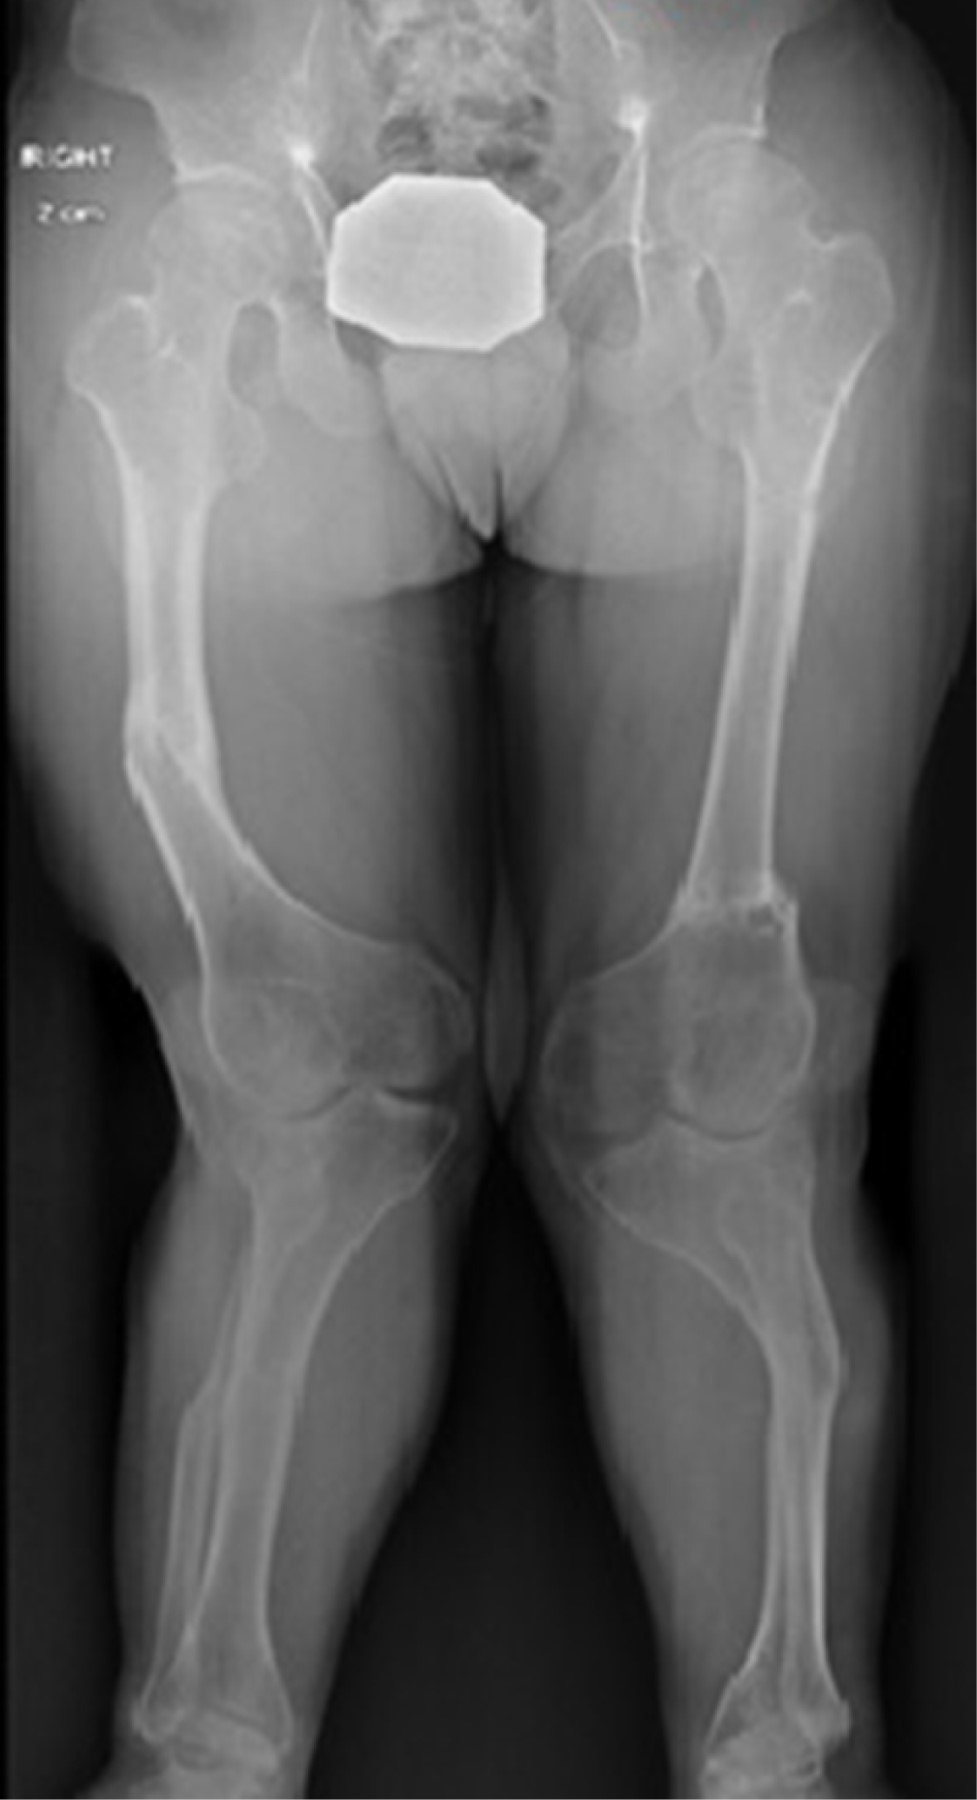

Se realizó la toma de radiografías panorámicas y segmentarias para una mejor planeación quirúrgica. Se encontró depresión articular a nivel de plataforma tibial lateral bilateral, con deformidad en valgo de rodillas de 48o y MAD de 104 mm derecho y 198 mm izquierdo, aLDFA (ángulo anatómico distal femoral lateral) 72o/70o, aMPFA (ángulo anatómico proximal femoral medial) de 110o/110o.

En esta paciente se decidió iniciar con crecimiento guiado por la edad. Intentando lograr la mayor corrección posible, tomando en cuenta lo poco predecible del crecimiento óseo en estos pacientes. Iniciamos con su primera cirugía a la edad de 10.4 años, siendo una hemiepifisiodesis tibial proximal medial bilateral y femoral distal medial bilateral con placas en 8 (Figura 5).

Posterior a tres años, a la edad de 13.3 años, se realizó retiro de las placas en 8 de ambos fémures y de manera simultánea se realizó osteotomía de alineación de fémur bilateral con fijadores externos articulados.

Un año después se efectuó la tercera intervención, siendo el retiro de placas en 8, además de osteotomía de alineación y desrotadora de ambas tibias con fijador externo articulado.

Figura 5